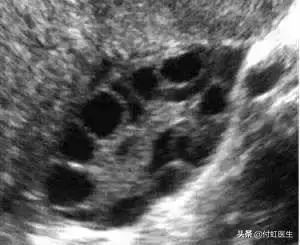

3. B超:临床医生可以通过超声检测卵巢体积、基础窦卵泡数目(AFC)、卵巢动脉血流来评估卵巢储备功能,其中基础状态(月经第2~3天)的卵巢体积变小与卵巢储备的原始卵泡减少、卵泡生长的数目少有关。

窦卵泡数AFC减少,窦卵泡指早卵泡期直径2~9mm的卵泡,通常认为双侧卵巢窦卵泡数合计少于5~7个提示卵巢储备功能下降。

对于涓涓2次化验FSH轻度升高的情况,付虹医生目前的带教老师刘教授建议她再做盆腔B超检查一下窦卵泡数AFC,以及基础抗苗勒管激素(AMH)水平,综合判断卵巢功能。

做B超检查我们看到,涓涓的窦卵泡数AFC,左侧卵巢4-6mm的卵泡10个,右侧卵巢4-6mm的卵泡8个,属于正常状态。